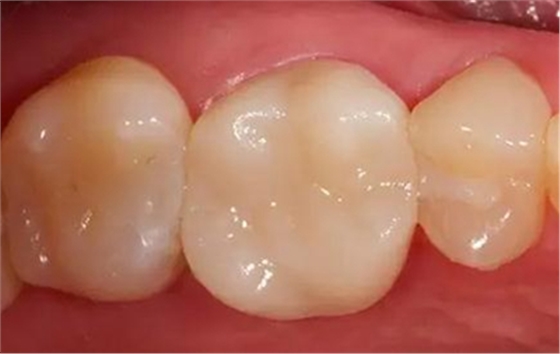

最終修復(fù)冠

拋光后的修復(fù)冠。由VITA SUPRINITY材料制作, 選擇1M2-HT。